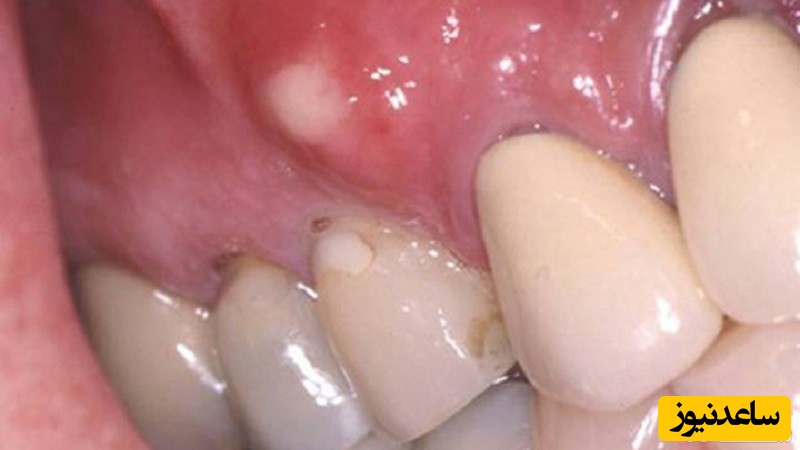

آبسه های دندان

پیاز: باقرار دادن یک تکه پیاز خام روی دندانی که درد می کند، می توانید از درد آن تا حدی بکاهید. پیاز ویژگی ضدمیکروبی دارد که می تواند در کنترل دندان در موثر باشد. برخی از مردم معتقدند پیاز حتی از مسکن های قوی هم موثرتر است. پیاز آبسه دندان را نیز درمان می کند. آن را روی دندان دردناک گذاشته و با ملایمت گاز بگیرید تا آبش خارج شود.